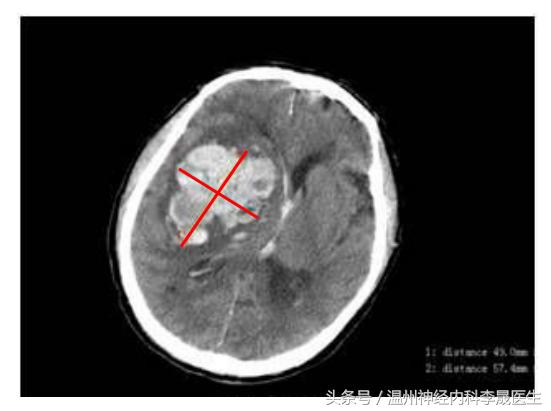

最大层面测量图

选取血肿最大层面,测量长宽径线,如果在胶片中,可以比对下方的刻度,一小格为1 cm。

出血量≈4.90×5.74×5.0÷2≈70 ml,但未包括破入脑室的出血量。